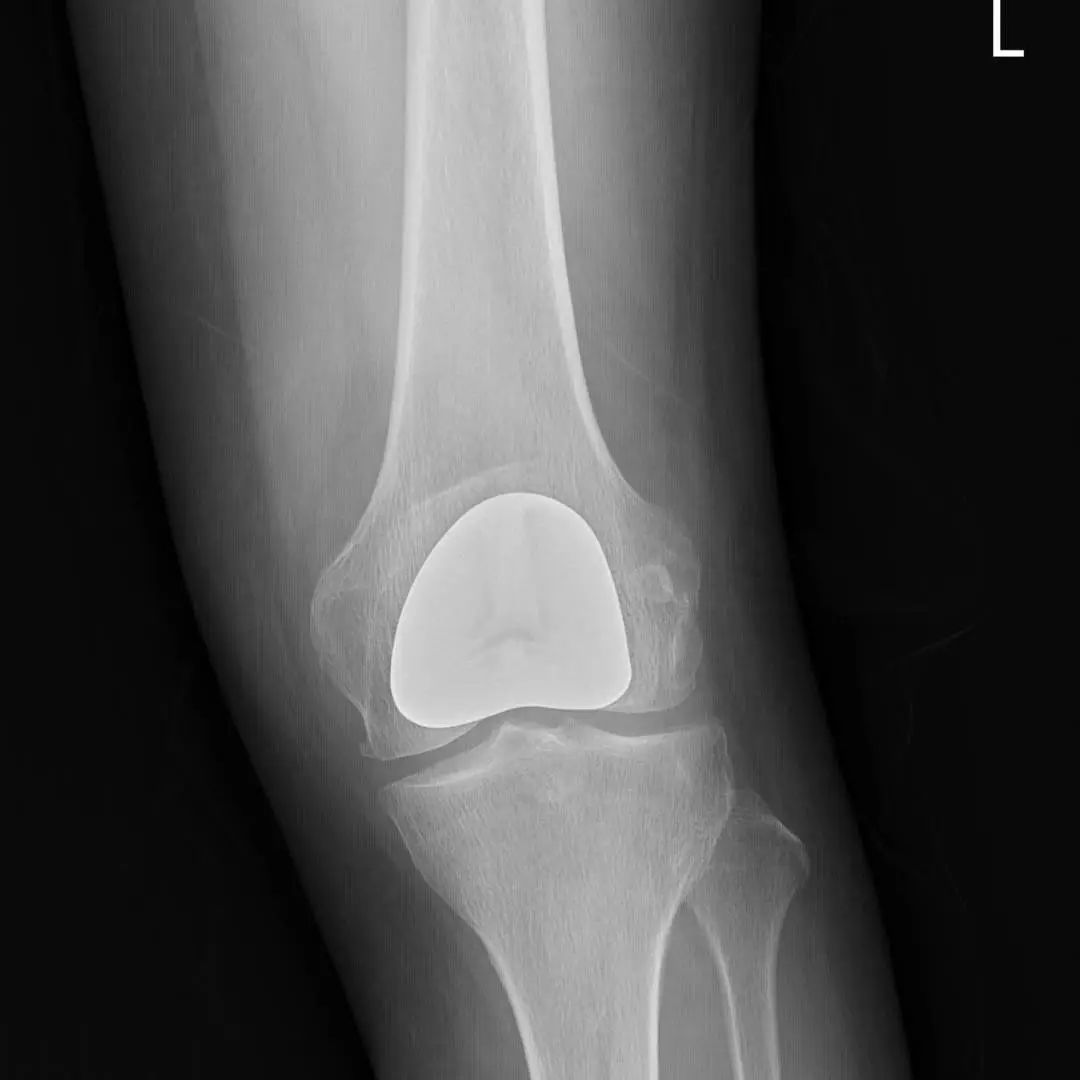

67岁的邵阿姨,双膝关节疼痛10余年,疼痛主要集中在屈伸膝关节时髌骨下。长期口服及外用药物治疗效果欠佳,反复加重,双膝的x线检查提示主要为髌股关节的退行性骨关节炎。程飚主任结合患者症状,影像学结果,体格检查,发现邵阿姨主要问题集中在髌股关节,膝关节间隙,内外侧髁,胫骨平台均可,为解决邵阿姨痛苦,尽可能保留关节,程飚主任决定对邵阿姨进行双侧膝关节的髌股关节表面置换,截骨量较少,邵阿姨第二天就能下地活动了,屈伸关节也不痛了,对手术疗效表示非常的满意。

部分膝关节置换手术目前已是非常成熟的治疗方法,亦属于保膝治疗的一种。主要包括单髁置换,髌股关节置换。单髁置换主要把膝关节内侧髁或者外侧髁表面已经磨损的部分替换成金属的假体和高分子聚乙烯耐磨垫片。髌股关节置换主要把髌股关节表面已经磨损的部分替换成金属的假体。

病变局限于髌股关节的患者,可行髌股关节表面置换;

同时有髌股关节及单侧髁的病变,可行单髁+髌股关节表面置换。